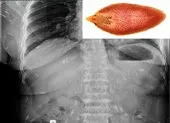

Ngày 23-3, thông tin từ Viện Sốt rét – Ký sinh trùng – Côn trùng TP.HCM cho hay vừa ghi nhận một trường hợp nhiễm sán dây nhiều năm và tiến hành cho uống thuốc xổ ra một con sán dây dài 2m.

Trước đó, anh VVQ (41 tuổi, ngụ TP.HCM) đến Viện Sốt rét – Ký sinh trùng – Côn trùng để kiểm tra sức khỏe. Khai thác tiền sử, các bác sĩ được biết bệnh nhân có triệu chứng rối loạn tiêu hóa và đi cầu ra phân có đốt sán đã 10 năm, tuy nhiên chỉ tự mua thuốc uống tại các tiệm thuốc tây và cơ sở y tế tư nhân. Anh cho hay khi uống thuốc vài tháng thì không thấy đốt sán rơi ra nữa nhưng ngưng thuốc một thời gian thì lại thấy.

Con sán dây dài 2m ký sinh trong ruột người đàn ông. Ảnh: BSCC

BS Chuyên khoa 2 Hồ Ngọc Quý, Viện Sốt rét – Ký sinh trùng – Côn trùng TP.HCM cho hay theo kinh nghiệm bằng mắt thường, loại sán người đàn ông nhiễm là sán dải heo, dân gian gọi chung là sán xơ mít. Thuốc sổ giun định kỳ có tác dụng trên một số loại giun ký sinh ở ruột non của vật chủ là con người như giun đũa, giun móc, giun tóc, giun kim… ít hoặc không có tác dụng đối với các loại ký sinh trùng ký sinh lạc chỗ như giun đũa chó mèo, sán chó, sán xơ mít…